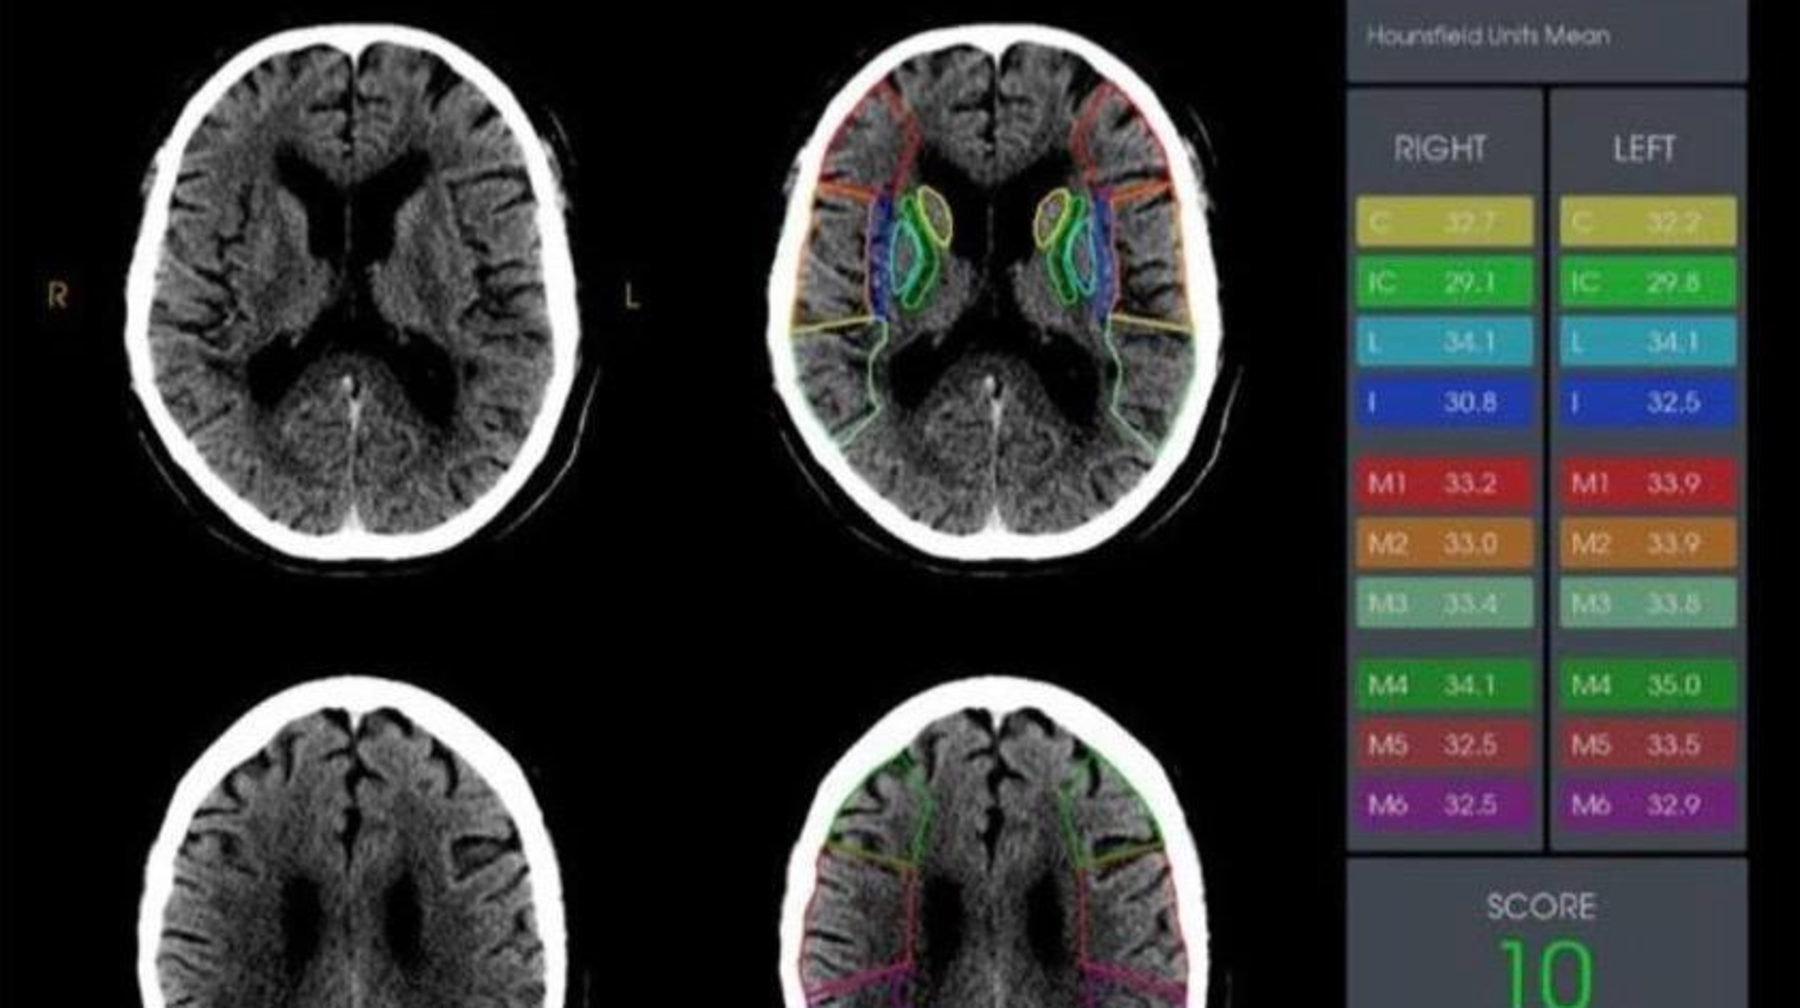

Pasıentke jedel túrde kompúterlik tomografıa (KT) júrgizildi. Qan quıylýdyń nemese ıshemıanyń qalyptasqan oshaǵynyń aıqyn belgileri anyqtalmaǵanyna qaramastan, KT derekteri RAPID- mamandandyrylǵan jasandy ıntellekt baǵdarlamasymen qosymsha óńdeldi. Bul júıe ınsýlttyń belgilerin erte anyqtaýǵa jáne trombty alyp tastaý operasıasyn júrgizýdiń kerektigin anyqtaýǵa múmkindik beredi.

Dáriger ıshemıalyq ınsýlt kezinde ýaqyttyń sheshýshi mańyzǵa ıe ekenin atap ótti:  hırýrgıalyq aralasý neǵurlym erte jasalsa, mı jasýshalary soǵurlym az zaqymdalady jáne tolyq qalpyna kelý múmkindigi anaǵurlym joǵary bolady. Qoldanylatyn RAPID baǵdarlamasy mıdy ASPECTS shkalasy (0-den 10 balǵa deıin) boıynsha baǵalaıdy jáne ortańǵy mı arterıasy baseınindegi zaqymdaný dárejesin anyqtaýǵa kómektesedi.